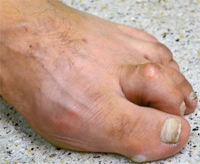

For this a modern minimum invasive Procedure, the so-called arthroereisis is available for some years. Through a small incision of no more than 2 cm, a special invented screw is inserted into the lower ankle. Important soft tissues or joints wont be stiffened or destroyed.

Flatfoot raising comes by the the screw. After two weeks a normal ist load possible. The Screw can be removed after 2-3 Years, the improved foot positions remains.